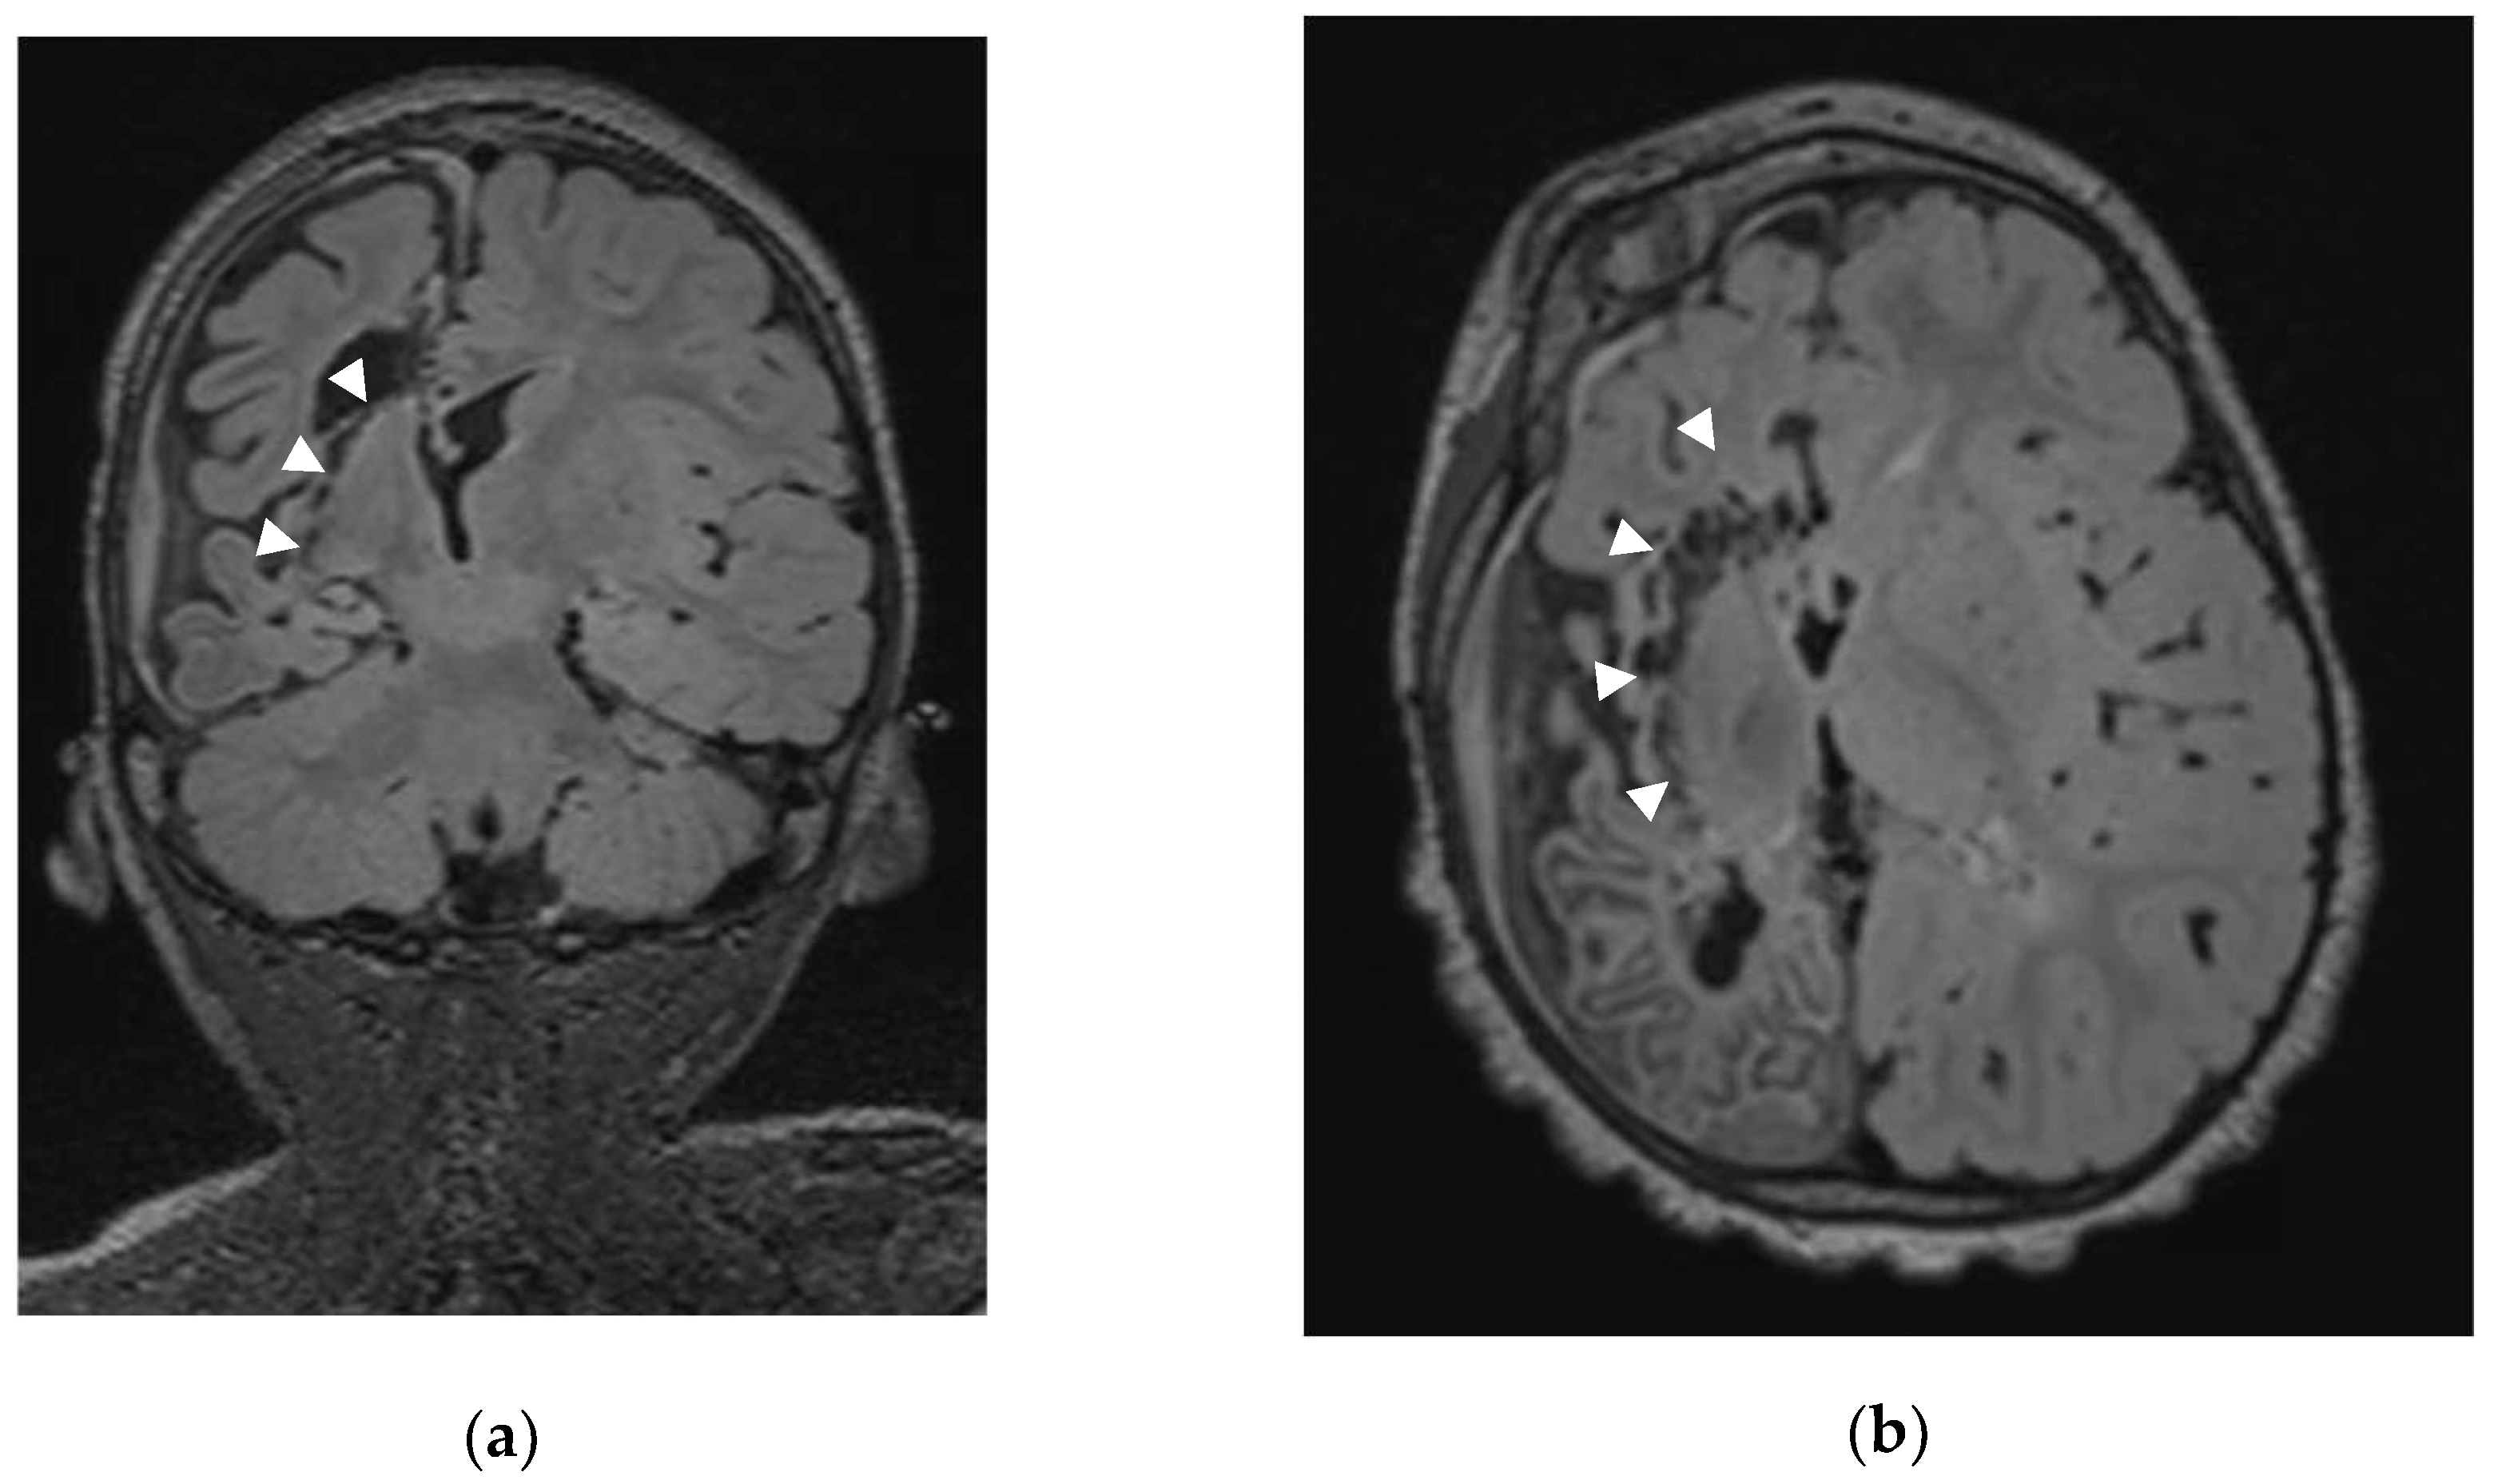

Figure 1. Axial (a) and Coronal (b) MRI of Patient 21 (Sturge Weber Syndrome) with arrow showing the sub-insular disconnection with preservation of the lenticular nucleus.

After dural opening with maximal preservation of the bridging veins we perform, under the operative microscope, a minimal precentral parenchymal resection (pallium and body of corpus callosum; ≤ 20 mm by ≤ 10 mm). Once the ventricle body is opened and the interventricular foramen of Monro identified, we occlude it with a thin rectangular Gelfoam sponge (Pfizer Inc®, New York, USA) to avoid blood contamination of the distal ventricular system. Using the ultrasonic aspirator (CUSA Excel® Integra LifeSciences®, Princeton, New Jersey, USA) we perform the anterior corpus callosotomy (genu and rostrum) followed by a sub-rostral resection of the posterior part of the gyrus rectus, of the cingulum and posterior part of the Brodmann area 25. Our next step consists in the splenium disconnection down to the great cerebral vein of Galen. Then the ventricular trigone floor is disconnected; during that step, we disconnect not only the crus (posterior column) of fornix but also the intralimbic and limbic gyri up to reach the posterior part of the ambient cistern. Once this step is completed, we reach the posterior part of the temporal horn and perform the posterior-anterior sub-insular trans-claustral disconnection staying as much as possible lateral to the lenticular nucleus (Figure 1).